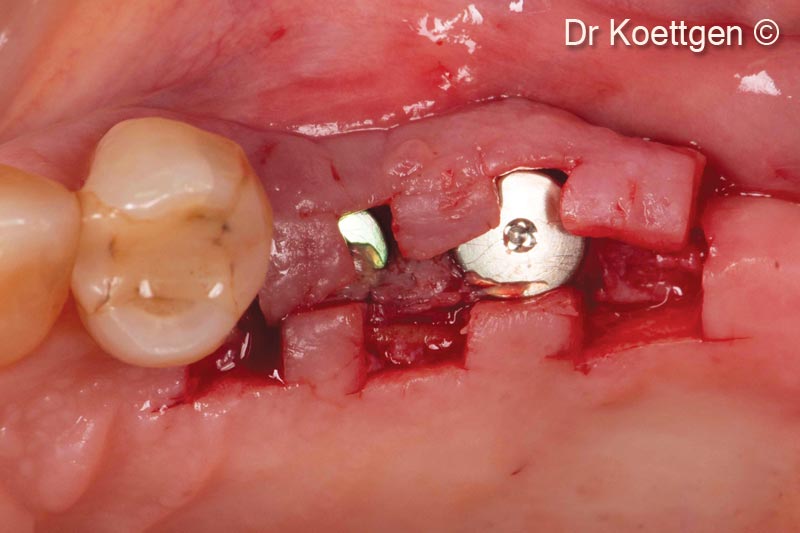

10. Uncovering with split finger technique 3 months after implantation

11. Uncovering with split finger technique 3 months after implantation